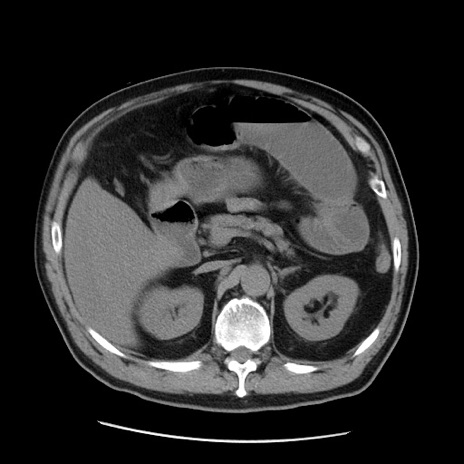

症例20(横断像)

【症例】 60歳代男性

【主訴】 腹部膨満、嘔吐

【現病歴】5日前頃より倦怠感を認め食事量減少し4日前の朝嘔吐、食事摂取困難となった。 3日前近医受診し点滴施行され整腸剤などを処方された。 当日他院を受診し、腹部膨満著明、炎症反応の上昇(CRP10.8、WBC11200)あり、紹介受診となる。

【身体所見】 意識JCS1 受け答えがはっきりしないBP 111/57mHg、 P 67bpm、、BT35.2°C、SpO2 97%(RA)、 腹部:膨隆、打診で鼓音あり、全体的に圧痛有り、腸蠕動音(-)、反跳痛ははっきりせず。

【データ】WBC 11400、CRP 14.20